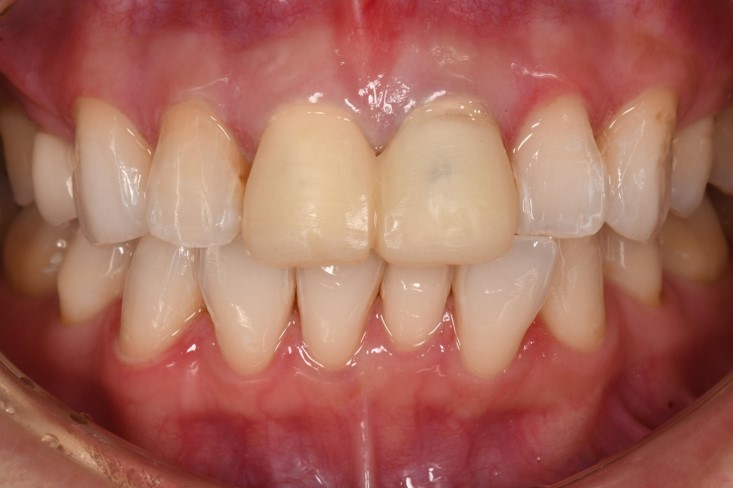

初診口內照,前牙美觀不良

術前、術後比較